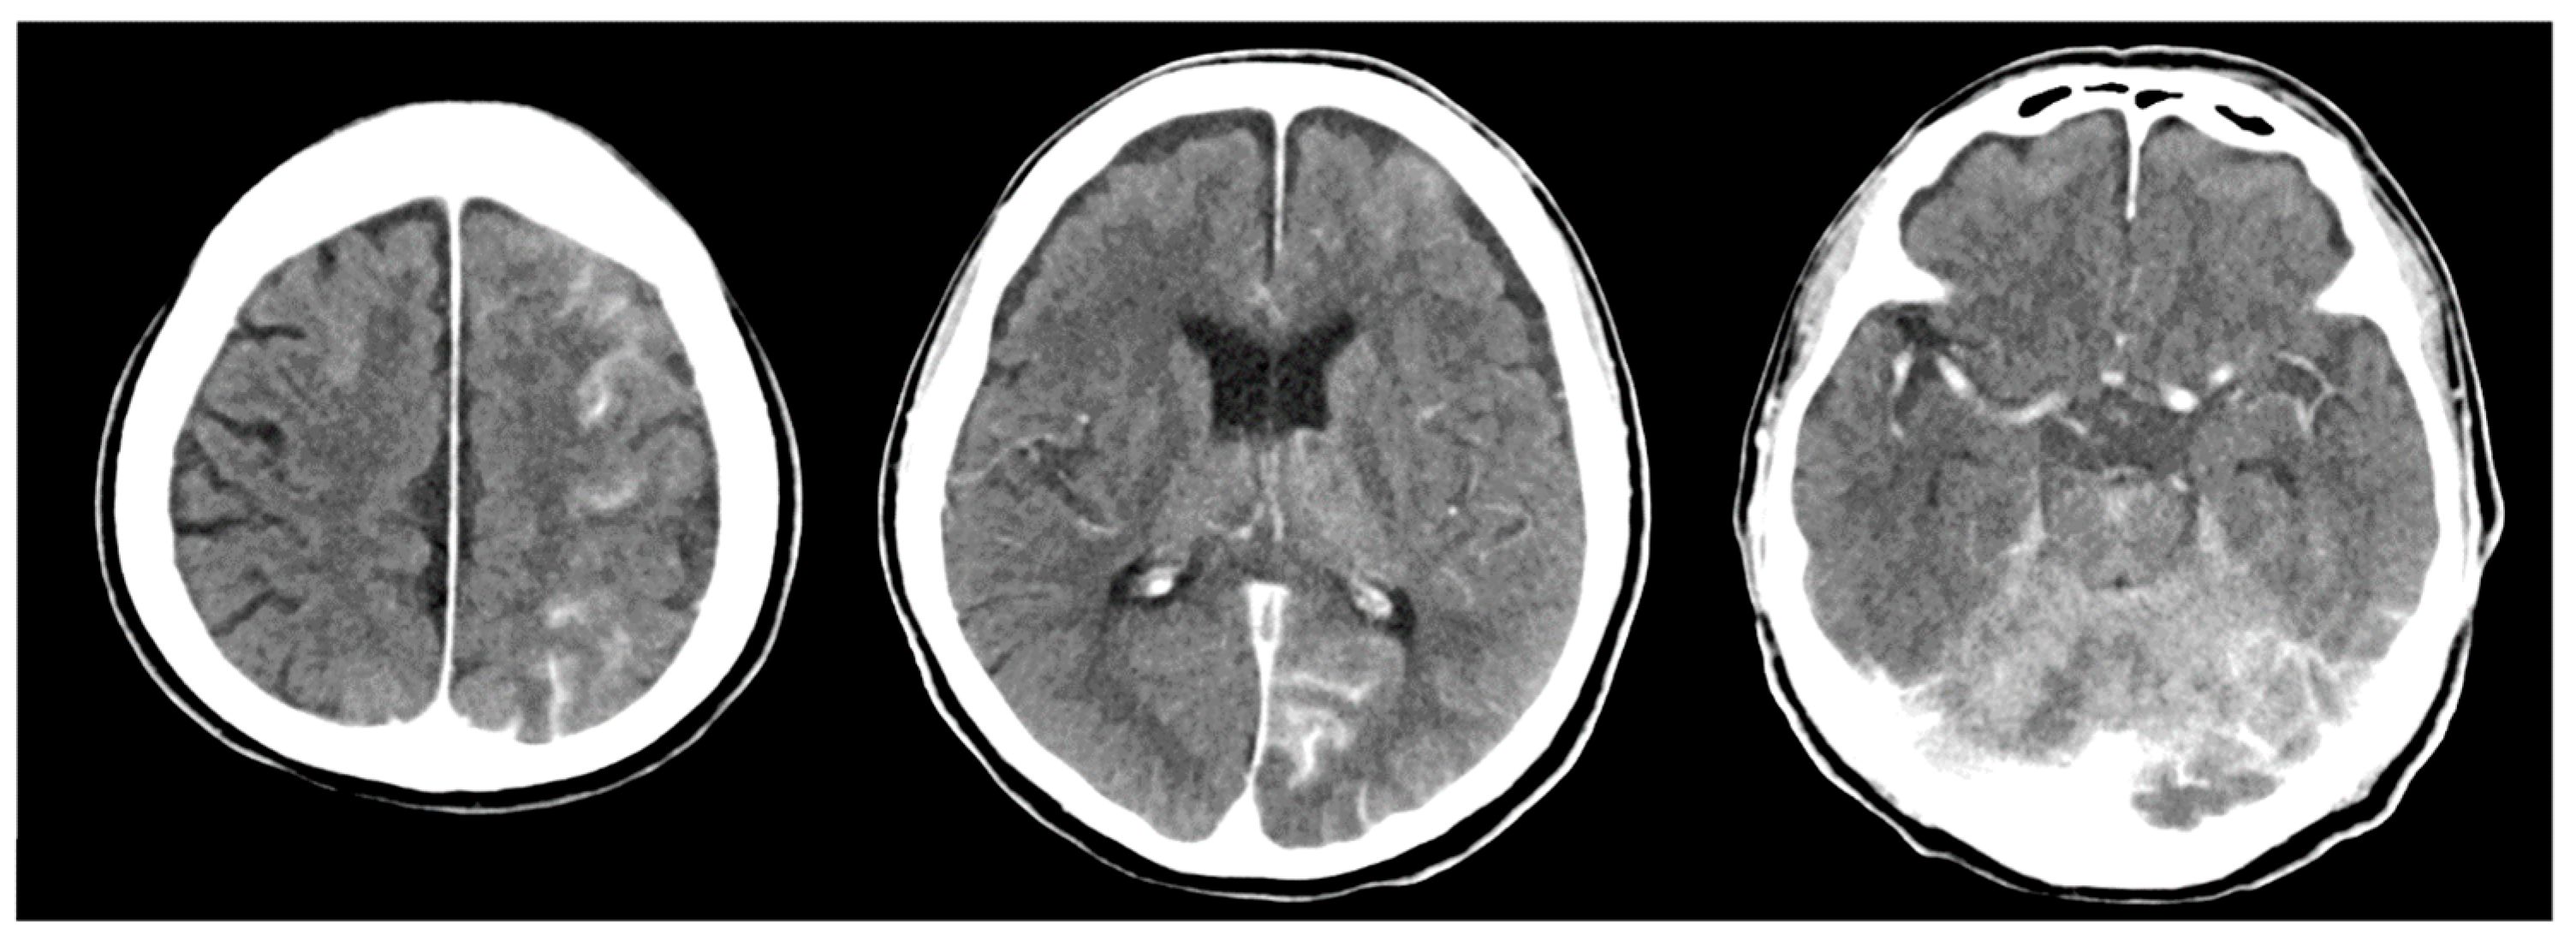

2. Case Description